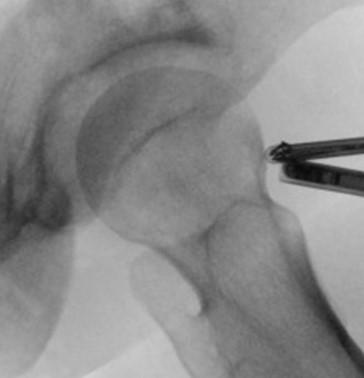

Es stehen uns eine Reihe klinischer Tests zur Verfügung bei denen es v.a. bei Beugung und Innendrehung des Hüftgelenkes zur Schmerzprovokation kommt (Impingement-Tests). Eine Röntgenuntersuchung (hoch eingestellte Beckenübersichtsaufnahme und eine axiale Aufnahme des Hüftgelenkes) ist notwendig um sich eine Gesamtübersicht über den Ausprägungsgrad der Formveränderung zu verschaffen. Anhand dieser Untersuchungen wird eine sog. Coxometrie durchgeführt, bei der das Hüftgelenk in digitaler Form vermessen wird. In der Regel wird zusätzlich eine spezielle Magnetresonanztomographie (hochauflösende MRT-Untersuchung mit radiärer Schichtführung durch den Schenkelhals und die Pfanne) durchgeführt, welche die dreidimensionale Darstellung der Formveränderung und die exakte Lokalisation eines begleitenden Labrumschadens möglich macht. Eine Infiltration des Gelenkes mit einem Schmerzmittel kann dazu dienen, einen Gelenkschmerz von anderen Schmerzursachen zu differenzieren, welche außerhalb des Gelenkes liegen. Eine Ultraschalluntersuchung kann das Vorliegen eines Leistenbruches ausschließen, welcher ähnliche Symptome verursachen kann wie ein mechanischer Konflikt im Hüftgelenk.

Das Labrum an der Hüfte ist eine knorpelige Lippe, welche die Hüftgelenkspfanne begrenzt und damit die Gelenkfläche vergrößert. In der Folge eines Impingement-Syndroms oder nach Verletzungen kann es zu einer Schädigung oder sogar einem teilweisen Abriss des Labrums kommen. Zur Diagnose eines Labrumschadens sollte eine hochauflösende Magnetresonanztomographie (MRT-Untersuchung mit radiärer Schichtführung) erfolgen. Hierbei kann es notwendig sein, Kontrastmittel (zusammen mit einem Schmerzmittel) in das extendierte Hüftgelenk (Traktions-MRT) zu infiltrieren, um die Bildauflösung zu verbessern und damit die Darstellungsgenauigkeit einer Labrumläsion zu erhöhen.

Für die Diagnose ist eine gründliche Untersuchung notwendig. Zusätzlich wird in der Regel eine Röntgenuntersuchung und evtl. eine Ultraschalluntersuchung bzw. sogar eine MRT Untersuchung benötigt. Durch eine Punktion des Hüftgelenkes kann die Diagnose gesichert werden. Hierdurch können sowohl die Gelenkflüssigkeit untersucht als auch antientzündliche Medikamente in das Hüftgelenk gespritzt werden.

Meist kann das Gelenkschnappen durch eine sorgfältige Untersuchung festgestellt werden. Insbesondere bei Innenrotation und Beugung der Hüfte kann das Schnappen durch den Untersucher provoziert werden. Zum Teil kann es auch von Patienten selbst ausgelöst werden. Durch eine Ultraschalluntersuchung kann eine Entzündung der Sehne oder des Schleimbeutels festgestellt werden. Anhand der Röntgenuntersuchung können bereits eintretende knöcherne Veränderungen festgestellt werden, die das Gelenkschnappen begünstigen. Intraartikulär kann eine entzündliche Veränderung der Sehnen anhand einer MRT Untersuchung festgestellt werden. Durch eine Injektion mit lokalen Betäubungsmitteln kann die Diagnose gesichert werden.

Beim internen Gelenkschnappen kann durch eine Hüftgelenksarthroskopie die Sehne des M. Psoas eingekerbt werden, was das Gelenkschnappen verhindert. Auch bei liegender Hüftprothese können die Sehnen eingekerbt oder gelöst werden und damit die Ursache für das oft schmerzhafte Schnappen beseitigt werden.